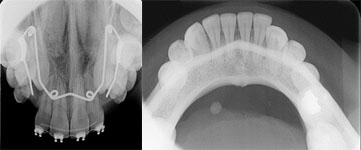

در این نوع رادیوگرافی قسمت بیشتری از دندانها و استخوان فک دیده می شود و از رسپتورهای بزرگ استفاده می گردد.بیشترین مورد استفاده از این روش در بررسی دندانهای نهفته و استخوان در هر دو فک و بررسی کف دهان وغدد بزاقی در فک پایین می باشد.تصویر سمت راست نمونه ای از نمای اکلوزال در فک پایین و تصویر سمت چپ نمونه هایی از نمای اکلوزال در فک بالا را نشان میدهد.

تصویر سمت راست نمونه ای از نمای اکلوزال در فک پایین و تصویر سمت چپ نمونه هایی از نمای اکلوزال در فک بالا را نشان میدهد.